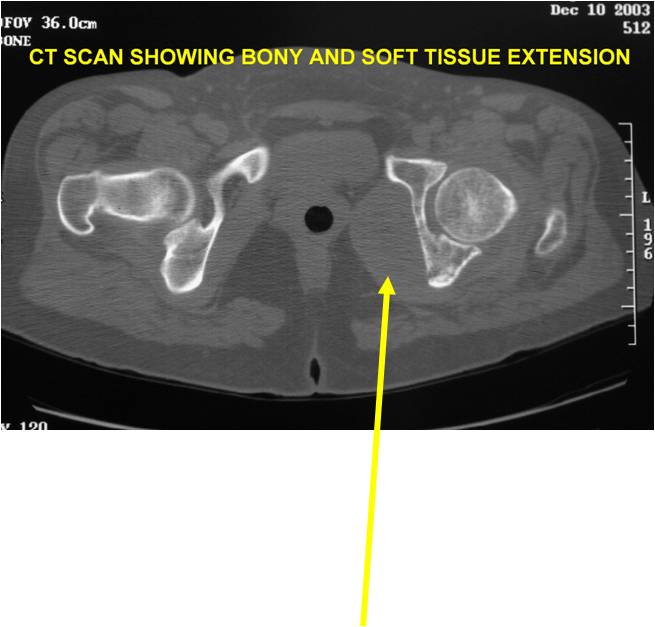

Radiology emulates pathology: Biphasic Tumor

- One region low grade chondrosarcoma

- Second more aggressive area with bone destruction, lysis of calcification, soft tissue mass

- Cortical permeation and a soft tissue mass in 70% of cases

Ill-defined, lytic intraosseous lesion

- Or extraosseous soft tissue mass

- Devoid of calcifications in continuity with lesions having the features of a cartilaginous tumor

Characteristically abrupt transition between chondroid tumor and dedifferentiated, lytic component

Bone may be expanded and adjacent cortex thickened

(Right Arrow)Aggressive Lytic Area (Dedifferentiated Sarcomatous Component) Cortical Destruction Soft Tissue Mass without Calcification